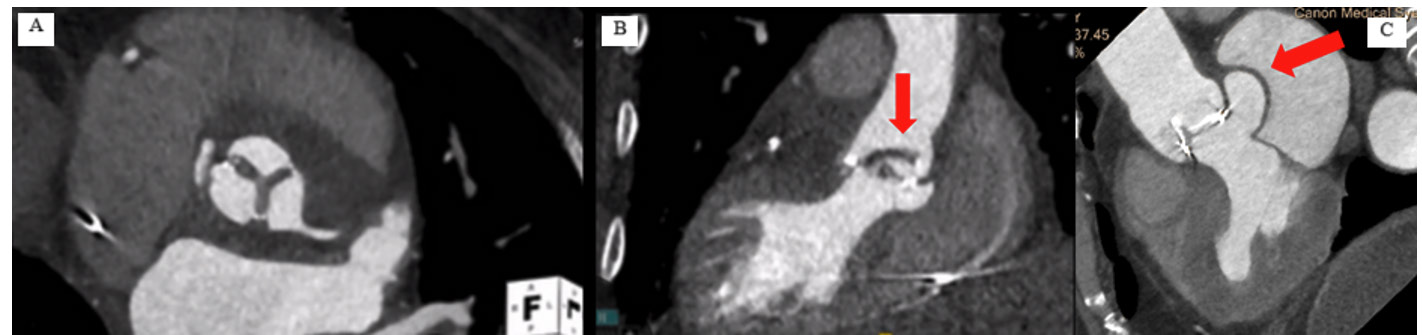

En cas d'insuffisance aortique sur prothèse, l'ETO permettra de localiser la fuite, plus facilement avec l'utilisation de sondes tridimensionnelles. Le scanner est également utile grâce à son excellente résolution spatiale permettant l'analyse des cusps de la prothèse et l'évaluation de lésions para-prothétiques (abcès, pseudo anévrysmes) (5) (Figure 2), la recherche de thrombus ainsi que l'analyse du mouvement des cusps en séquences ciné (6).

Figure 2. Endocardite infectieuse sur bioprothèse aortique avec épaississement des 3 cusps (A) et volumineuse végétation (B). Endocardite infectieuse sur bioprothèse aortique avec désinsertion de la partie postérieure de la prothèse responsable d'une fuite péri-prothétique très sévère (flèche) (C).